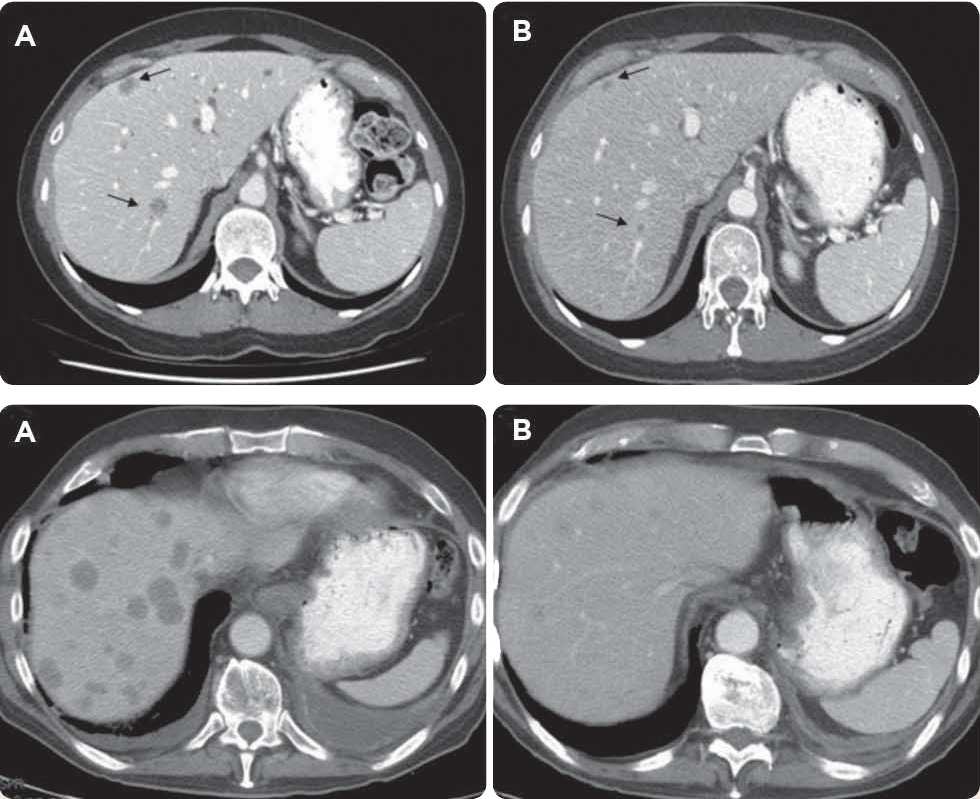

Unfortunately, in the interim, she developed multiple bilateral liver lesions and punctate pulmonary nodules consistent with distant disease (Figures 2A, 2B, and 3A).

Given Ms. S.G.'s continuing excellent performance status, further treatment was recommended. Based on recent published literature, a regimen of cisplatin at 80 mg/m2 day 1, vinorelbine at 25 mg/m2 day 1 (repeated every 28 days), and weekly cetuximab (VCC) at 250 mg/m2 was initiated. Remarkably, following three cycles of treatment, despite receiving multiple prior lines of chemotherapy, her restaging CT scan demonstrated complete radiographic response of the intrathoracic disease, stable response of the anorectal mass, and near-complete resolution of the hepatic lesions (Figures 3A and 3B).